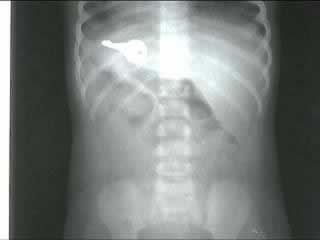

5,磁铁碎块——身份不明的美国男孩

X光片显示,这个男孩一次吞下了一块磁铁分成的几个碎片,而当它们进入小男孩的胃里后,这些磁铁碎片又相互吸引,吸附在了一起。”。